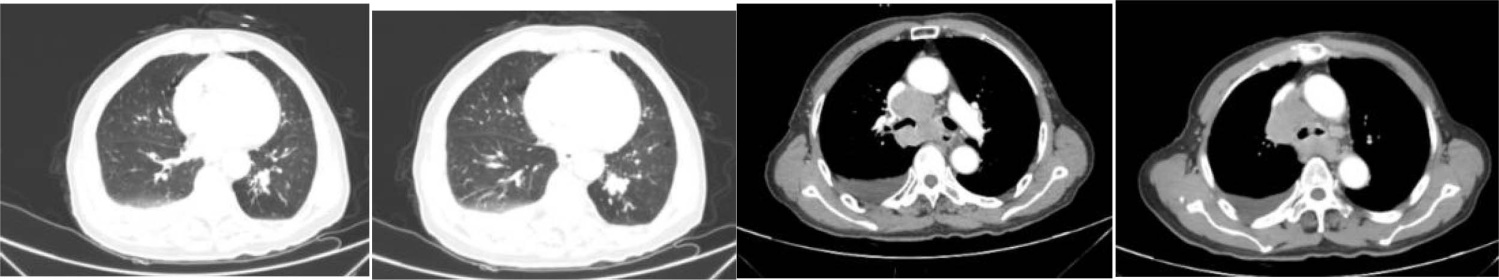

胸部CT:双肺渗出性改变。双侧胸腔少量积液。支气管炎表现。纵隔淋巴结肿大(图5)。

Figure 5. Chest CT results

5. 胸部CT结果

胸部CT:左肺下叶后基底段气管不通并肺内高密度灶,考虑占位;纵隔多发肿大淋巴结,转移可能;双肺炎症,左前胸壁皮下结节,建议复查。(医院CT室)。

a) 胸部CT:诊断意见:左肺下叶占位,考虑肺Ca;结合临床。纵隔、左肺门淋巴结。胸壁软组织结节,考虑转移(图9)。

Figure 9. Results of chest CT examination

9. 胸部CT检查结果

影像学检查在多抗体阳性AE中常缺乏特异性。本例患者头颅MRI仅显示多发性脑梗死和脑白质脱髓鞘,未出现抗NMDAR脑炎常见的颞叶内侧高信号或抗GABABR脑炎的单侧/双侧颞叶异常[9]。这种“影像学阴性”表现约见于20%的多抗体阳性病例,可能与抗体对神经元功能的可逆性干扰而非结构性破坏有关[10]。胸部CT提示的左肺下叶占位及纵隔淋巴结肿大,结合神经元特异性烯醇化酶(94.24 ng/mL)和胃泌素释放前肽(>5000.00 pg/ml)的显著升高,高度提示SCLC的可能,而胸壁肿物病理检出的鳞状上皮细胞进一步支持恶性肿瘤的诊断[11]